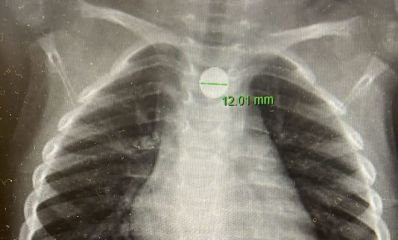

סוללת דיסק תקועה בוושט. צילום: דוברות מרכז רפואי מאיר מקבוצת כללית

בן 3 בלע סוללת דיסק והובהל לניתוח חירום במאיר